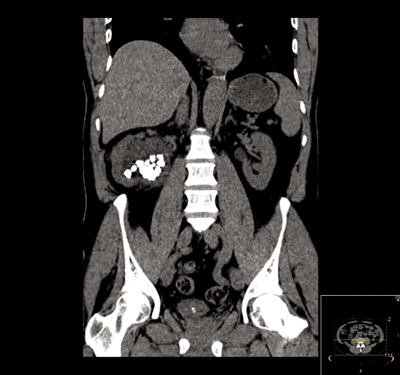

Figure 2.

The lower ureter was tortuous and of the ‘fish-hook’ type. A nephrostogram revealed a stricture at the vesicoureteric junction (VUJ) and incision of the VUJ using a Collins knife failed to demonstrate the lumen (Figure 2 and 3).